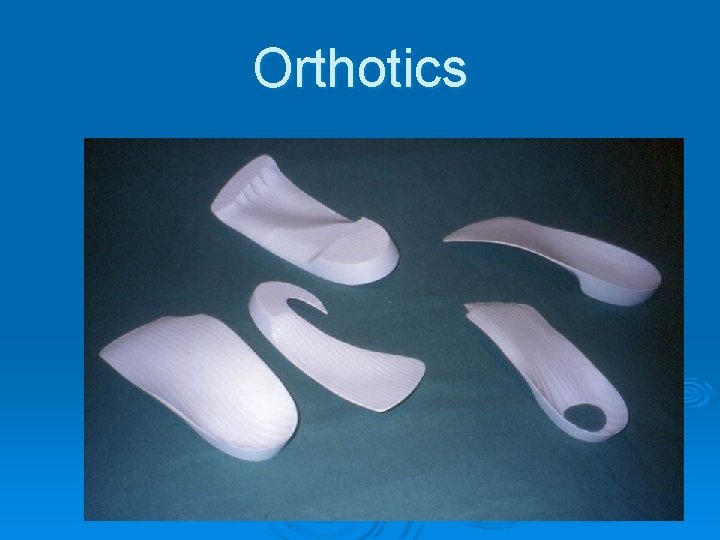

Orthotics

Orthotics

Orthotics